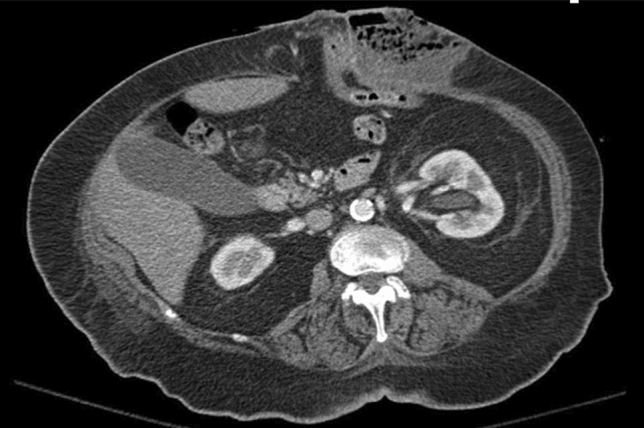

Case Presentation: We report a case of an 81-year-old male who presented to emergency department with incarcerated right inguinal hernia with small bowel contents. During his surgery, he was found to have the urinary bladder adhered to the hernia sac. The hernia sac and the urinary bladder were reduced without any complications. The patient underwent a Lichtenstein tension-free hernia repair.

Conclusion: Inguino scrotal hernia containing bowel contents is not uncommon; however, the presence of the urinary bladder is rare. It should be anticipated intraoperatively, particularly in patients with long-standing hernias. Management is surgical and Lichtenstein repair is a viable option with low rates of recurrence.